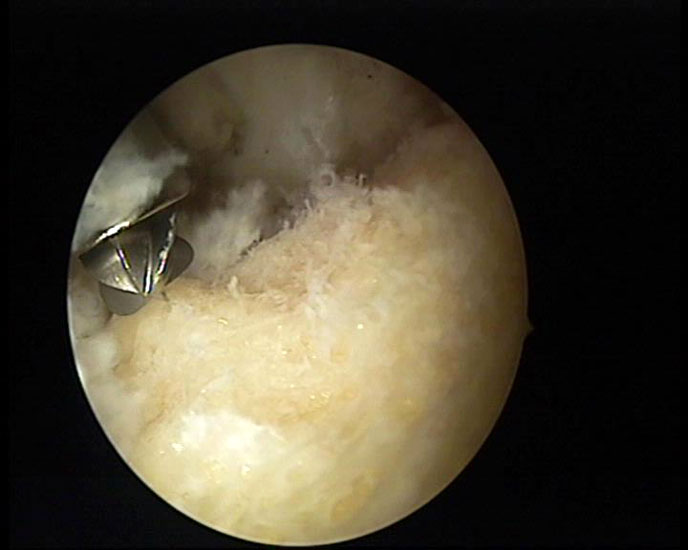

Abbildung 5-7, Video 2

Zunächst wird die Bursektomie (Abb. 5: gerötete Bursa subachillea; C=Calcaneus, B=Bursa, AS=Achillessehne) mit der Radiofrequenzsonde durchgeführt und die Haglundexostose dargestellt. Alternativ kann die Bursektomie mit einem Shaver durchgeführt werden. Hierbei sollte der Ansatz der Achillessehne kaudal einsehbar sein (Abb. 6: C=Calcaneus, AS=Achillessehne) und unbedingt die gesamte mediolaterale Ausdehnung der posterioren Calcaneusfläche erfasst werden (Abb. 7). Häufig liegen Anteile der Exostose weit medial und/oder lateral und werden übersehen.